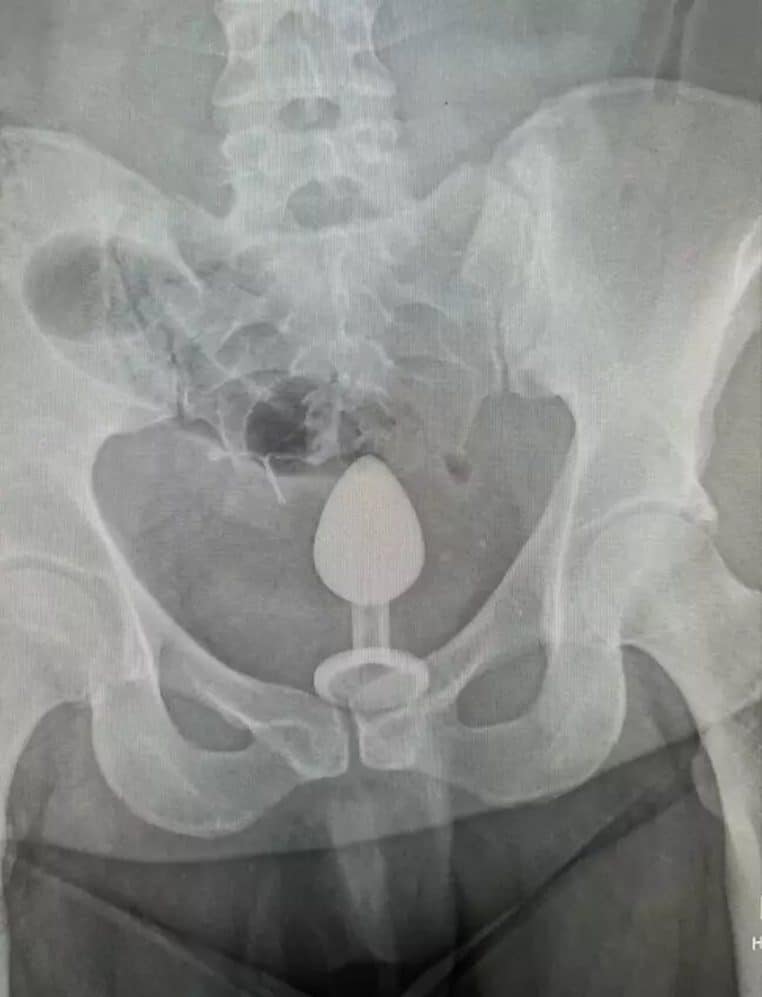

Après avoir contacté les secours, Gigi a été conduite aux urgences. Là-bas, les médecins ont rapidement identifié le problème sur la radio.

Si au départ, il a été question de se rendre au bloc pour extraire le corps étranger, l’un des médecins a proposé une alternative. Bien que plus douloureuse, elle exigeait uniquement l’utilisation de gants et de beaucoup de lubrifiant. Une solution qui a rassuré Gigi, qui craignait de se retrouver en salle d’opération.